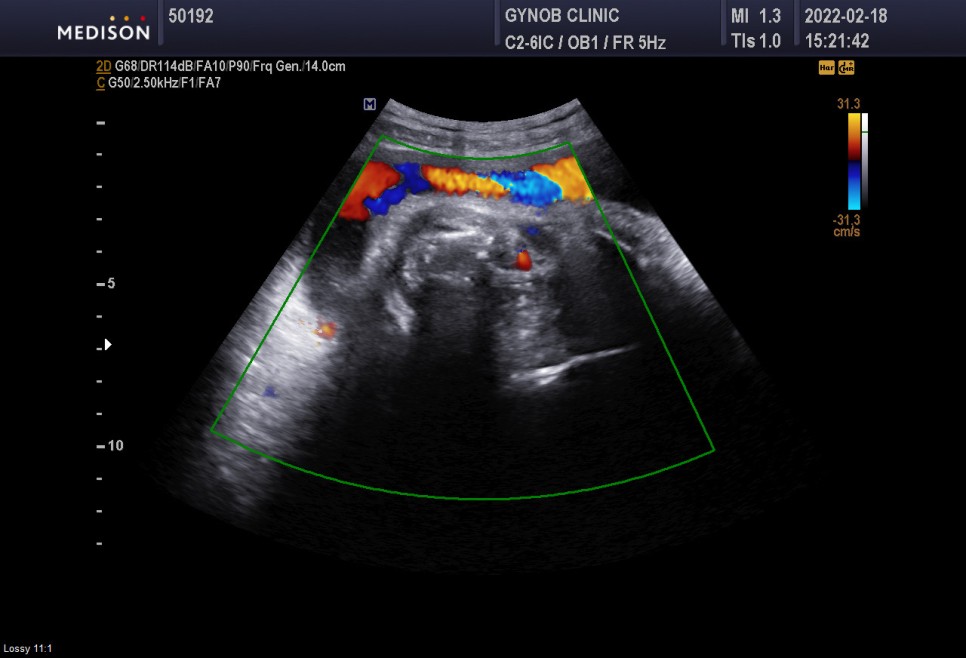

▲초음파실에서 초음파도 봤다=심상덕 원장님은 초음파를 5분 동안 꼬박꼬박 챙겨보신다.

아기의 머리 위치는 정상*경부 제대륜 1회 신경 쓸 필요는 없습니다.

- 경부 탯줄은 탯줄이 아기의 목 부분을 감고 있다는 것을 의미한다

경부제 대륜 1번 탯줄에 목을 1번 감고 있다는 뜻이다.너무 신경 안 써도 될 것 같아